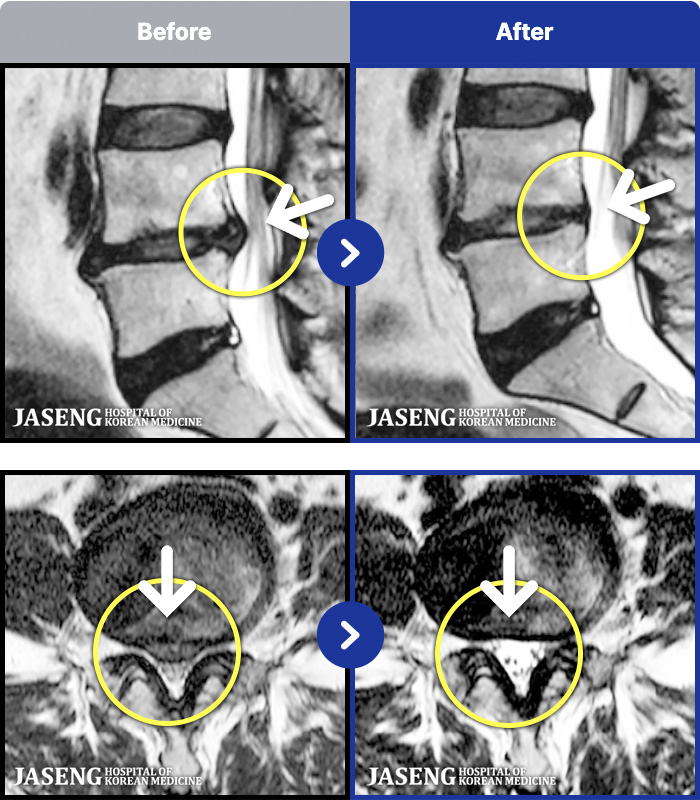

- MRI ġ

MRI ġ

191 MRI ũ ʸ Ȯϼ.

㸮 , , ⸳ Ƹ

[] 19.10.11~20.05.30

ȯںп Ǹ ǿ ԿǾ, ο ġ ۿ Ƿ ġḦ Ͻñ ٶϴ.